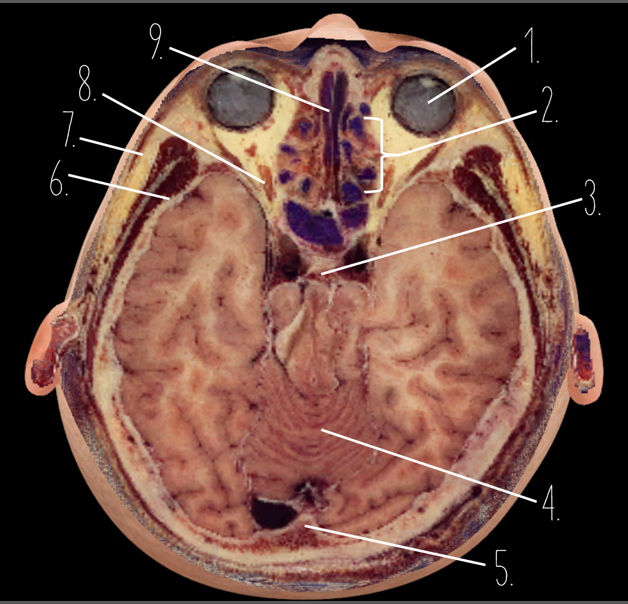

1?

Globe of Eye

2?

Ethmoid Sinus

3?

Pituitary Gland

4?

Cerebellum

5?

Internal Occipital Protuberance

6?

Wing of Sphenoid

7?

Zygomatic Arch

8?

Optic Nerve

9?

Vomer